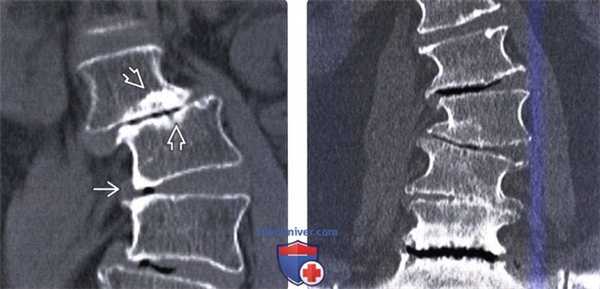

(Слева) КТ, фронтальный срез: признаки множественных аномалий сегментации позвоночника. Несколько правосторонних полу-позвонков не полностью сегментированы с соседними позвонками и формируют причудливую картину мальформации позвоночника с несколькими сколиотическими дугами искривления.

(Справа) 3D-реконструкция КТ этого же пациента с врожденным сколиозом на фоне множественных аномалий сегментации позвонков позволяет более полно охарактеризовать вклад каждой из имеющихся аномалий позвонков в деформацию и помогает выстроить наиболее оптимальный план лечения. (Слева) Фронтальная 3D-реконструкция: правосторонний L3 полупозвонок, являющийся причиной врожденной правосторонней сколиотической деформации. Слева на уровне этого полу позвонка видны рудиментарные корень дуги и задние элементы позвонка.

3. КТ после инструментальной стабилизации сколиоза позвоночника:

• Оценка консолидации на уровнях спондилодеза, выявление зон просветления вокруг винтов

• Оценка состоятельности металлоконструкций

• Выявление врожденных аномалий развития позвонков (полупозвонки, сросшиеся позвонки)

• 3D-реконструкции могут оказаться полезными при предоперационном планировании и послеоперационном обследовании пациента